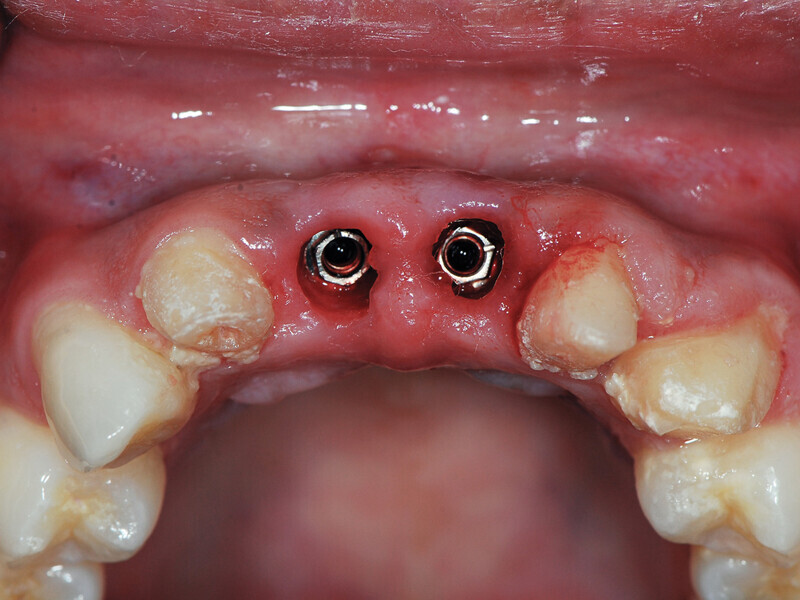

Fig. 8: Picasso Lite+ diode laser removing soft tissue to uncover the implants’ cover screws. (Photo provided by Dr. Gregori M. Kurtzman)

Fig. 9: Uncovery of the implants and healing screws exposed. (Photo provided by Dr. Gregori M. Kurtzman)

Fig. 10: Healing abutments placed into the implants. (Photo provided by Dr. Gregori M. Kurtzman)